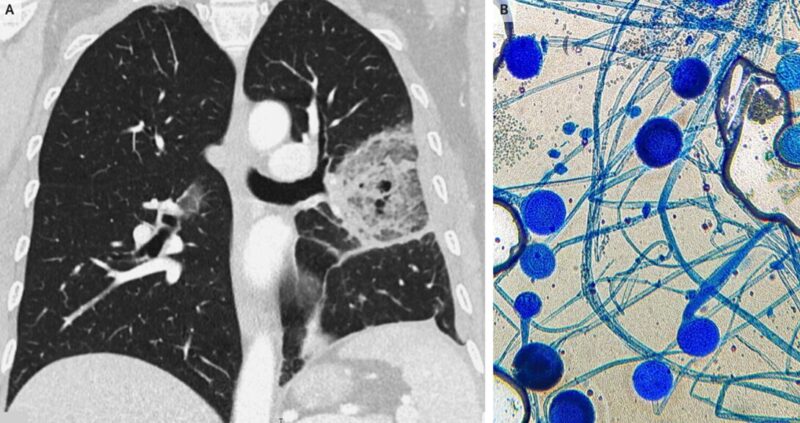

胸部CTでは、密な硬化リングに囲まれたすりガラス状の不透明な領域が示された。これは逆ハローサインとして知られている。気管支肺胞洗浄が施行され、ラクトフェノールコットンブルー染色(糸状菌の形態の観察に優れる染色法)にて糸状菌であることが同定され(B)、培養結果からムコール感染であることが同定された。

「肺ムコール感染症」と診断。

本症例ではリポソームアムホテリシンBによる治療が開始され、手術が計画されたが、患者は発症から15日後に死亡した。